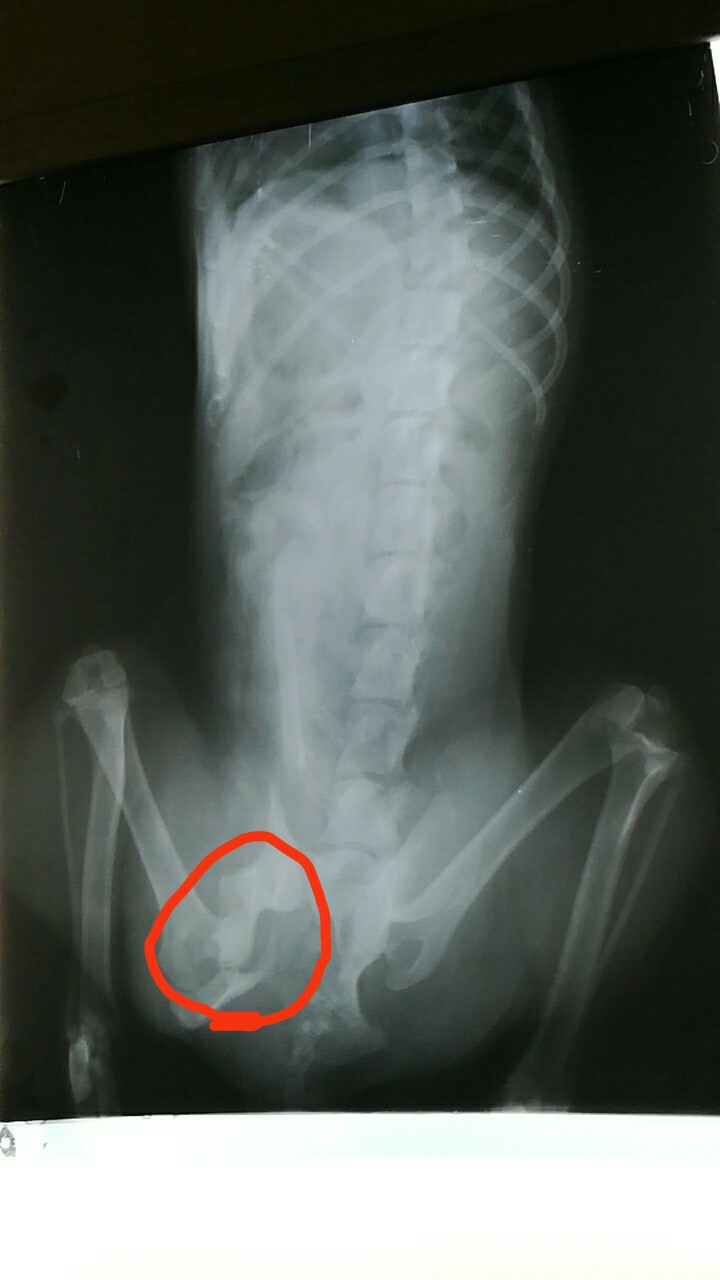

由于沒做絕育手術(shù),歡歡見到馬路對面有母狗在吸引,不顧一切掙脫主人的韁繩,跑向馬路對面只聽“哐”一聲被車撞到,緊急聯(lián)系我院,經(jīng)檢查左髖骨骨折。所以對于不以繁殖為目的狗狗要適齡絕育,避免因為發(fā)情期引起的車禍。